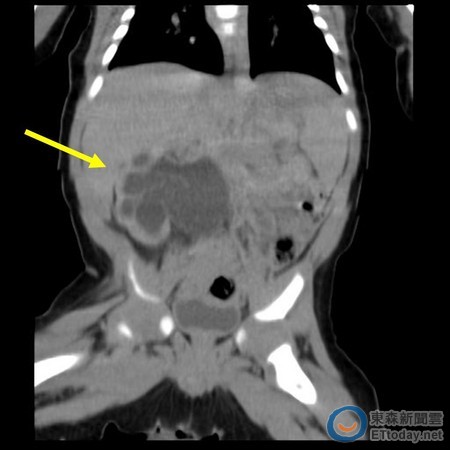

▲電腦斷層顯示黃小弟的右腎腫大如熊掌。(圖/台北慈濟醫院提供)

黃小弟7月出生後,到小兒科接受腹部超音波檢查,確定右側腎盂輸尿管狹窄,正常新生兒的輸尿管管徑為0.3~0.4公分,黃小弟卻只有0.1公分,不僅尿液阻塞,腎臟也從正常的3X5公分,腫脹到5X6公分,體積足足大了三倍,跟一個熊掌差不多大,已喪失三分之一的功能,若不緊急手術打通輸尿管,恐怕將造成腎衰竭,將來甚至容易得敗血症而死亡。